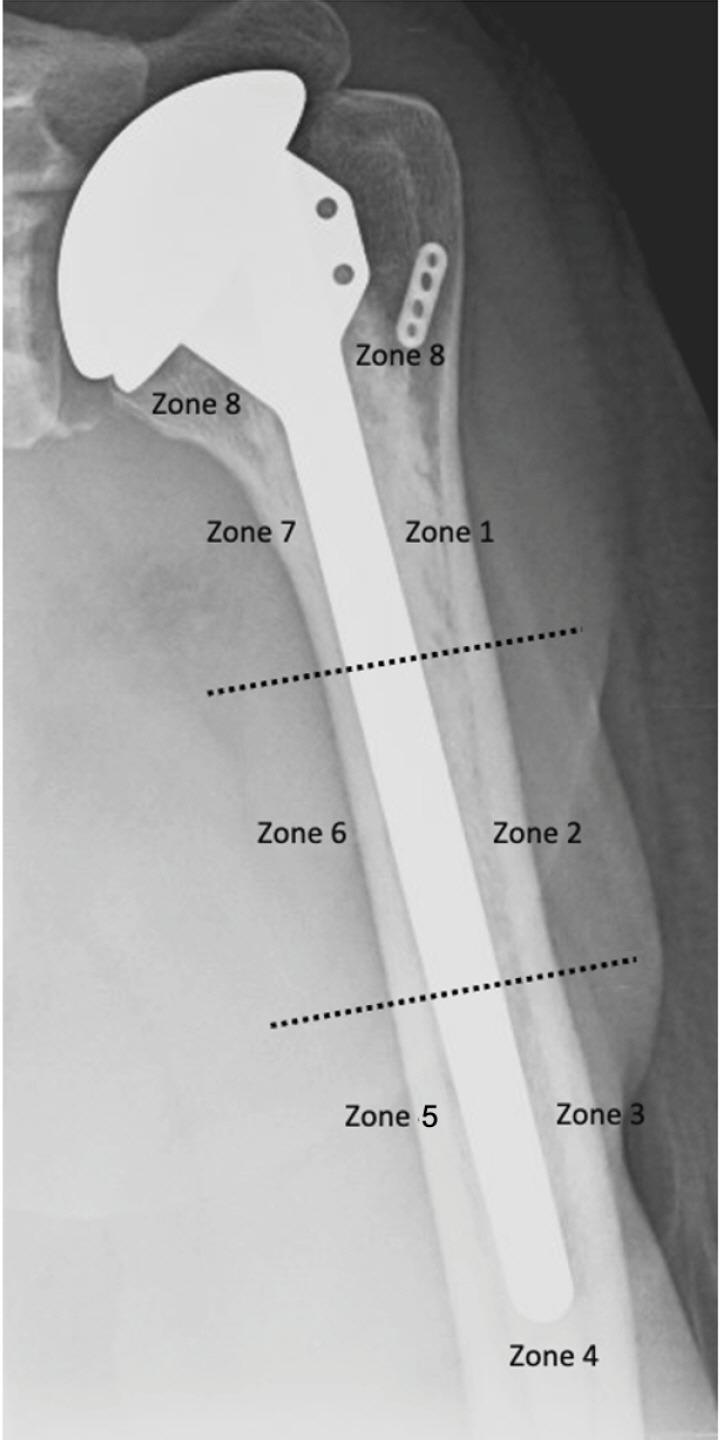

This study retrospectively analyzed 169 shoulders that required primary anatomic total shoulder arthroplasty (aTSA). Shoulders were stratified by humeral stem fixation technique: cementation or press-fit. Data were collected pre- and postoperatively. Primary outcome measures included range of motion, patient reported outcomes, and radiographic measures.

One hundred thirty-eight cemented humeral stems and 31 press-fit stems were included. Significant improvements in range of motion were seen in all aTSA patients with no significant differences between final cemented and press-fit stems (forward elevation: P=0.12, external rotation: P=0.60, and internal rotation: P=0.77). Patient reported outcome metrics also exhibited sustained improvement through final follow-up. However, at final follow-up, the press-fit stem cohort had significantly better overall scores when compared to the cemented cohort (visual analog score: P=0.04, American Shoulder and Elbow Surgeon Score: P<0.01, Simple Shoulder Test score: P=0.03). Humeral radiolucency was noted in two cemented implants and one press-fit implant. No significant differences in implant survival were observed between the two cohorts (P=0.75).